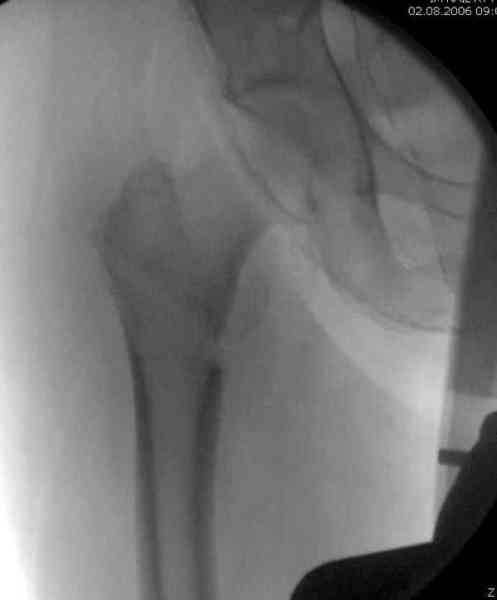

Александр Николаевич, как не прискорбно, я практически заканчивал эту операцию.

Изначально у оперируещего хирурга были только теоретичесике представления о ЗИМО с блокированием, планировался компрессионно-динамический остеосинтез стержнем S2 (Stryker).

Во время операции ни стол ортопедический,ни ДРУ не применялось (думалось, что сделают все на руках!)

Изначально была выбрана не правильная точка введения стержня, в связи с чем в конце, я подчеркну, в конце операции произошло из-за напряжения между прокимальным концом канала бедра и стержнем разрушение в/3 бедра.

Проволока наложена потому, что при введении штифта не прошли эту зону римером и произошли сколы на концах отломков.

Под ЭОП во время операции такого смещения не было. Мы бы конечно не отпустили этого больного с такой картиной (сами бы что-то сделали или к вам отпр).

Почему не сделали R-gr? Все банально для таких больниц как наша - не работал R-аппарат в течении 3х недель.(я сам увидел эти снимки у вас)